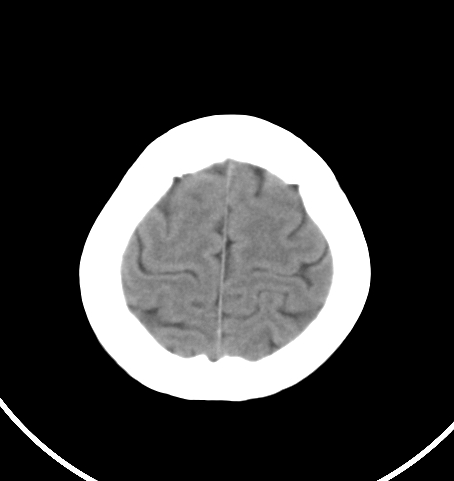

病人女 35岁 自述头晕 头痛

双侧基底节区及右侧丘脑区多发点状钙化,周围未见水肿及占位征象.余未见明显异常.考虑:脑囊虫病<囊虫的退变或死亡期>请结合有无相关病史.

未见明显异常,建议检查颈椎。